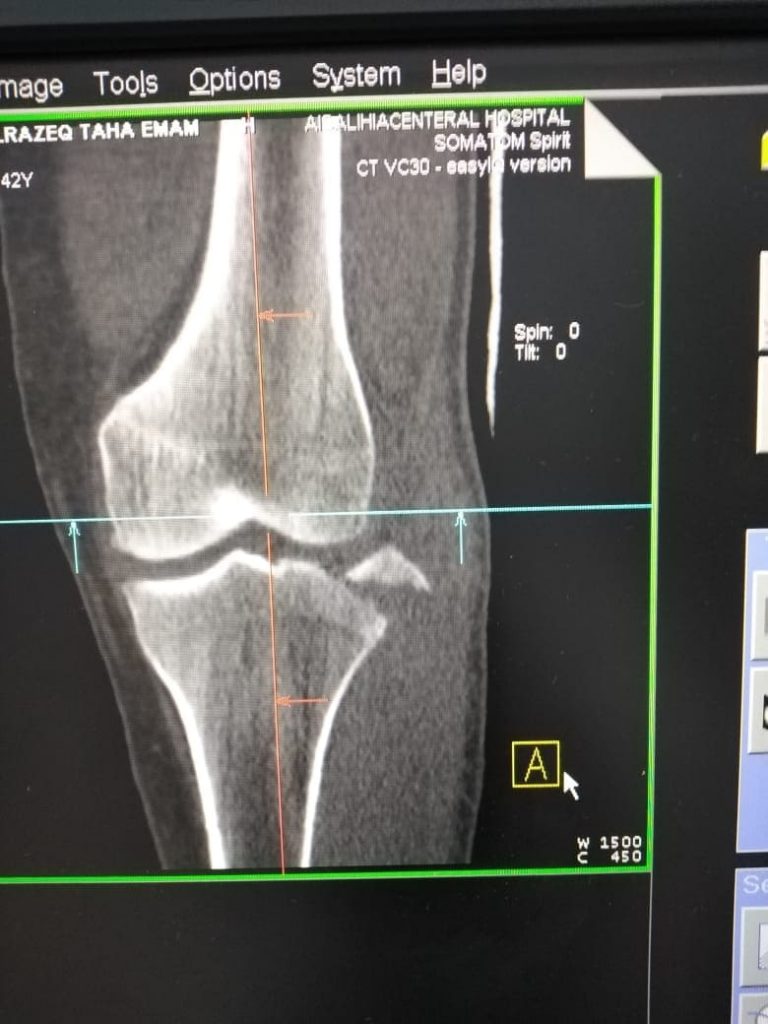

شارك الدكتور هاني مصطفي، والدكتور عمرو مديح أخصائي العظام، والدكتور محمد عفيفي أستشاري التخدير، وفنيين الأشعة، وهيئة تمريض العمليات بمستشفي الصالحية الجديدة، بإجراء عملية جراحية دقيقة لمريض يبلغ من العمر 24 عام، يعاني من كسر بمنتصف عظمة الفخد اليمني، وكسر بمفصل الركبة اليسري، وذلك بعد إجراء الفحوصات والأشعة اللازمة،

وقام الفريق الطبي بإجراء تثبيت لكسر الفخد الأيمن بمسمار نخاعي تشابكي، كما تم تثبيت كسر الركبة اليسري بمسامير خاصة للمفاصل، تحت جهاز الأشعة بالعمليات، والحالة الآن مستقرة وتحت الملاحظة الطبية، بإشراف مدير المستشفي.